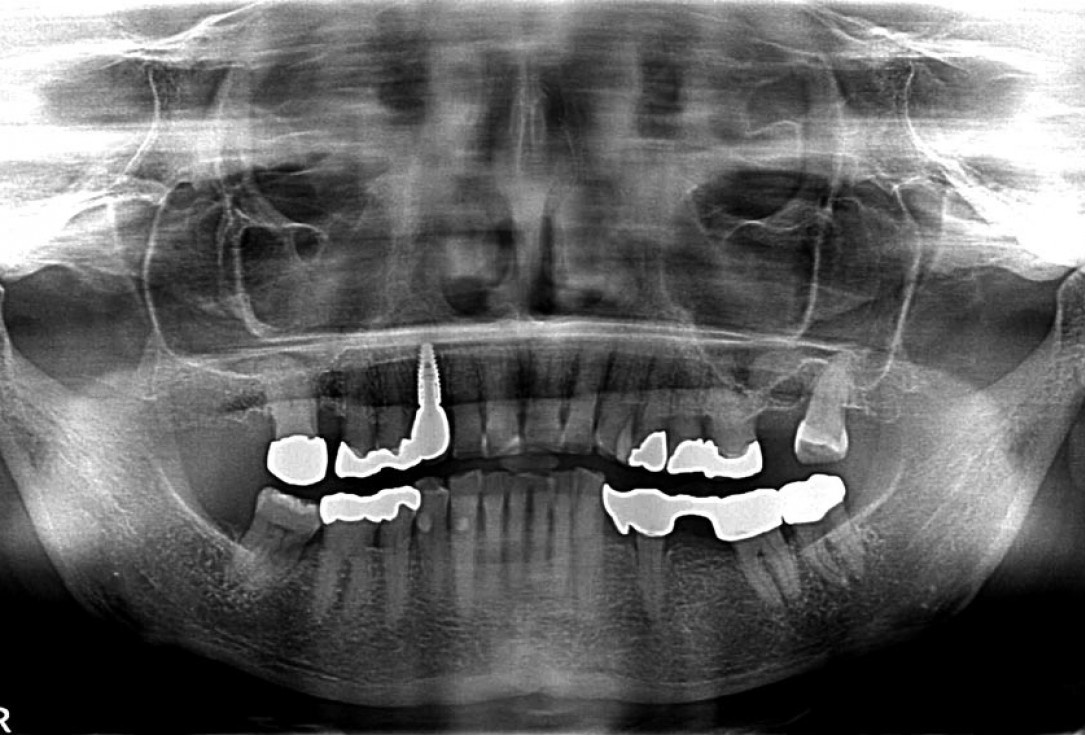

08/12 - X-ray scan post augmentation

Block augmentation with maxgraft® in the maxilla - PD Dr. Dr. F. Kloss

09/12 - CBCT scan 5 months post augmentation

10/12 - X-ray scan after implant placement